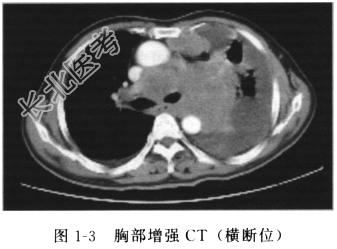

患者老年男性,因咳嗽、痰中带血、发热入院,既往吸烟多年。入院后增强CT(图1-3、图1-4)示:左肺门见不规则软组织影(大于7cm),多个纵隔淋巴结肿大,左侧胸腔积液。头颅MRI、腹部超声及全身骨ECT未见明显异常。肿瘤标志物NSE升高。胸腔积液细胞学检查,连续3次找到小细胞癌细胞。